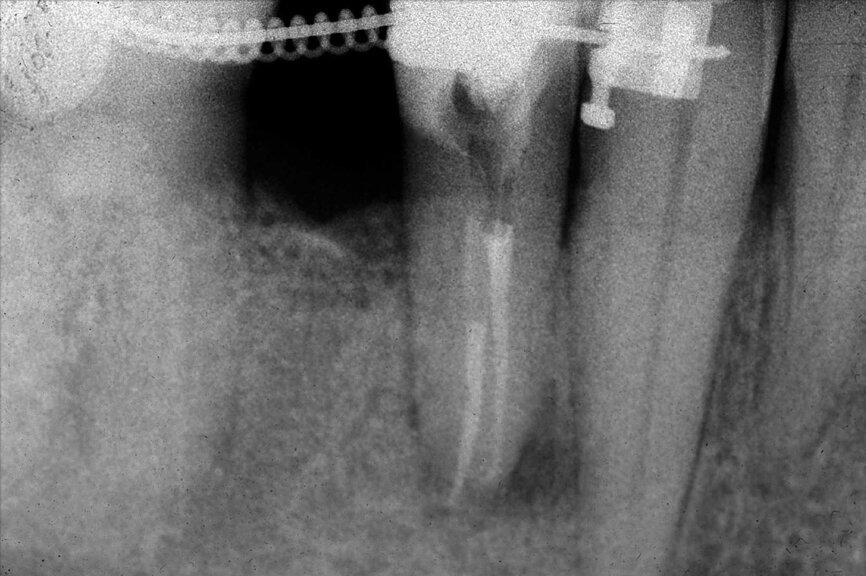

Il en va tout autrement pour la prémolaire mandibulaire présentée dans les figures 7 à 9 où, malgré l’absence de signes radiologiques de lésion et le traitement endodontique visiblement correct réalisé par un autre confrère, le patient se plaint d’une douleur persistante, qui est à la fois spontanée et déclenchée par un test de percussion de la dent. Dans ce cas, l’excellent traitement endocanalaire réalisé précédemment semble indiquer le besoin de recourir à une approche endodontique chirurgicale, susceptible de garantir un taux de réussite plus élevé que celui d’un simple retraitement. Étant donné le doute sur le diagnostic, nous avons décidé de réaliser un examen 3D et celui-ci révèle une lésion endodontique causée par un canal lingual resté sans traitement. Grâce à ce diagnostic exact, il devient possible d’envisager une intervention ciblée sur la pulpe restante, et de réaliser un traitement efficace du canal non traité.

L’évaluation CBCT préopératoire est utile dans les cas nécessitant une approche chirurgicale, non seulement pour confirmer la présence d’une lésion, mais aussi pour planifier l’intervention et, en particulier, identifier le type d’incision chirurgicale à pratiquer, en fonction de la taille et de l’emplacement de la lésion en question (Figs. 23–25). Le cas spécifique présenté dans cet article est caractéristique de cette situation. La radiographie intraorale n’a pas permis de déterminer l’étendue de la lésion, qui touche non seulement la région apicale de la prémolaire, mais aussi un segment édenté en distal. Cette région doit faire l’objet d’un traitement régénérateur, afin de garantir la cicatrisation appropriée de la zone, suivi par la mise en place d’une membrane. Une approche totalement différente de celle requise pour la chirurgie endodontique doit être utilisée pour protéger le lambeau. Les différentes étapes de l’intervention sont illustrées dans les images peropératoires (Figs. 26–28). L’examen CBCT réalisé 12 mois plus tard, confirme la cicatrisation complète de la lésion apicale et la parfaite intégration de la greffe (Figs. 29–31).